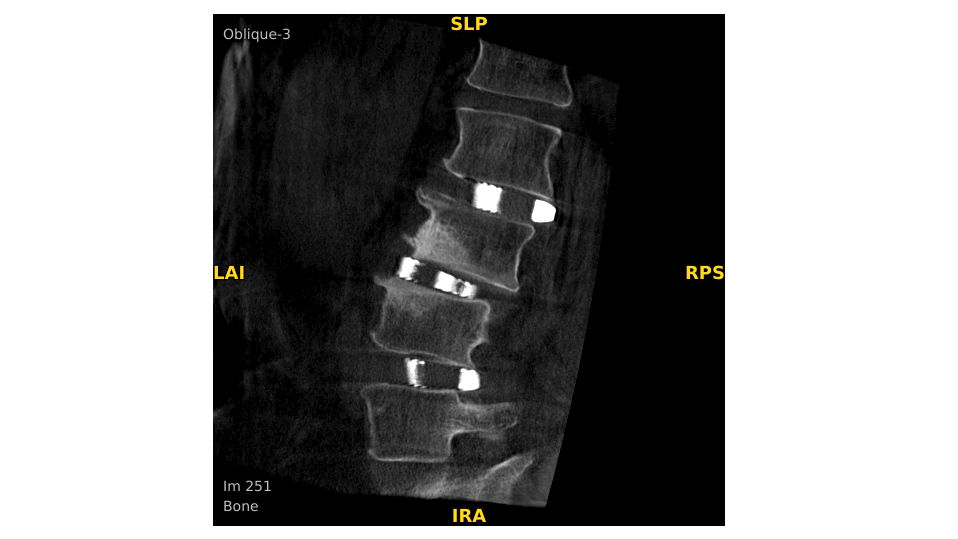

Analysieren Sie Ihre Scans mit dem GE Volume Viewer – genauso intuitiv wie am CT. Profitieren Sie von der vollständigen Darstellung axialer, koronarer und sagittaler Ebenen sowie von MIP-Ansichten und 3D-Visualisierungen im VR-Modus. Scrollen Sie durch bis zu 512 Schichten mit nahtloser Anpassung der Schichtdicke – für eine präzise Befundung direkt im OP.